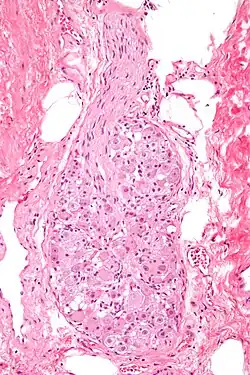

Sensible Ganglien enthalten die Nervenzellkörper (Soma) sensibler Neurone. Sensible Ganglien besitzen alle Rückenmarksnerven in Form der Spinalganglien. Sie enthalten pseudounipolare Nervenzellen und sind von einer Bindegewebskapsel umgeben, von der Trabekel in das Innere ziehen und im Inneren ein Stützgerüst, das Stroma, bilden. Auch die Hirnnerven III und VII bis X besitzen solche Ganglien, der VIII. Hirnnerv besitzt aber, im Gegensatz zu den übrigen, bipolare Ganglienzellen. Die Nervenzellen sensibler Ganglion nehmen über ihren Dendrit Informationen aus der Umgebung auf und leiten sie über ihr Axon an das Zentralnervensystem weiter.[1]

Autonome (Vegetative) Ganglien sind im Autonomen Nervensystem zu finden. Sie besitzen ebenfalls eine Bindegewebskapsel, mit Ausnahme der Ganglien in der Wand des Darms (intramurale Ganglien). Autonome Ganglien enthalten multipolare Nervenzellen. Im Gegensatz zu den sensiblen Ganglien erfolgt in den autonomen Ganglien eine Umschaltung auf eine zweite (postganglionäre) Nervenzelle über Synapsen. In diesen Ganglien werden also Informationen von einer auf eine andere Nervenzelle weitergeleitet.[1]